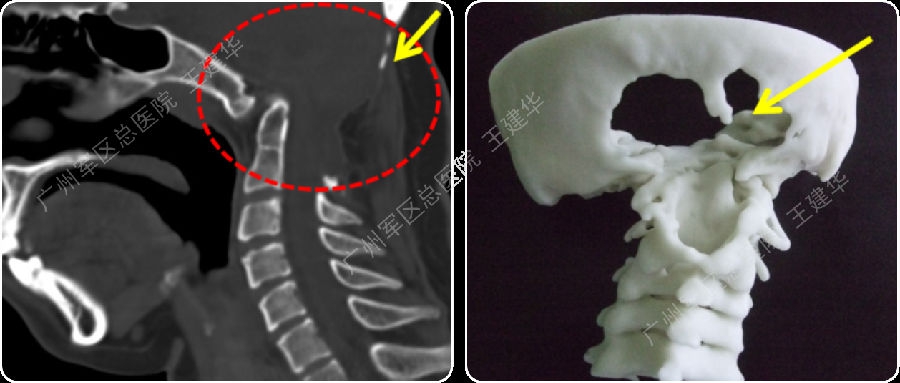

不稳定型颅底凹陷症(寰枕脱位型)

三维CT显示,患者曾行后颅窝减压手术

手术难点

(1)曾行后颅窝减压手术,骨质大量缺损,无法再行后路手术;

(2)寰齿之间及侧块关节之间有骨痂增生,阻挡复位。

术前术后对比